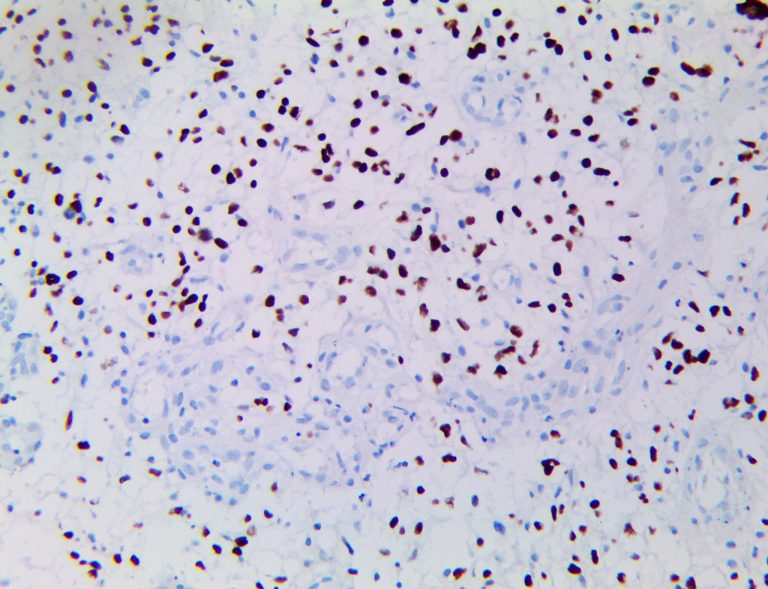

It is the ICU physician who is most likely to witness one of the deadliest manifestations of the abnormal immunological response, the cytokine storm syndrome (CSS). This response is also referred to by some as the cytokine release syndrome (CRS). CSS is characterized by continuous activation and expansion of macrophage and lymphocyte populations, which secrete large amounts of cytokines, causing the cytokine storm. This massive cytokine release is akin to hemophagocytic lymphohistiocytosis (HLH) disease, a syndrome characterized by initial unchecked and persistent activation of cytotoxic T lymphocytes and NK cells.

Clinical and laboratory manifestations of HLH include fever, enlarged liver and/or spleen, neurologic dysfunction, coagulopathy, liver dysfunction, cytopenias (i.e., low levels of erythrocytes, leukocytes, and/or platelets), hypertriglyceridemia, hyperferritinemia, hemophagocytosis, and eventually diminished NK cell activity as the immune system becomes progressively paralyzed. HLH can be familial (primary HLH) or secondary to another disease process (sHLH), such as rheumatic disease, in which it is referred to as macrophage activation syndrome (MAS, characterized by elevated ferritin).